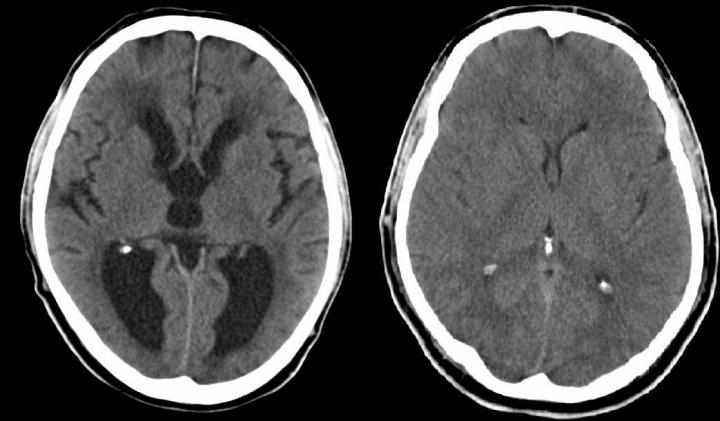

Here, Xu's team looked at overall brain development in mice without SNX27. They observed severe hydrocephalus, with fluid-filled cavities (ventricles) in the brain that were much larger than normal. Examining potential causes, they saw that these mice lacked the cells that normally line the ventricles and circulate fluid in the brain, called ependymal cells.